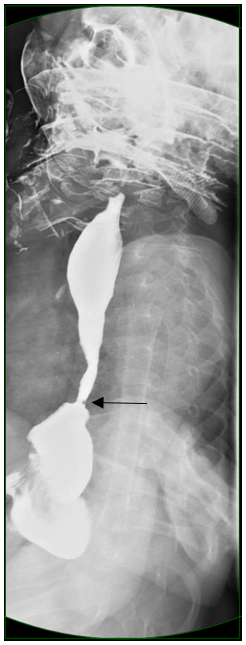

Subsequently, the boy successfully underwent a double-contrast upper GI study (Figures 1 and 2). An esophageal stricture was identified involving the lower one-third of the esophagus. The esophagus was foreshortened, with a moderate-sized hiatal hernia secondary to traction. Proximal esophageal dilatation was present. No gastroesophageal reflux (GER) was noted during examination; however, the findings were in keeping with chronic/recurrent longstanding GER with secondary esophageal stricture.

Figure 1. Upper GI series with barium contrast, lateral view. An irregular stricture is visible in the distal esophagus. Proximal dilation and a mildly foreshortened esophagus is evident. A hiatal hernia secondary to traction is visible. The intrathoracic gastroesophageal junction is indicated by the black arrow.